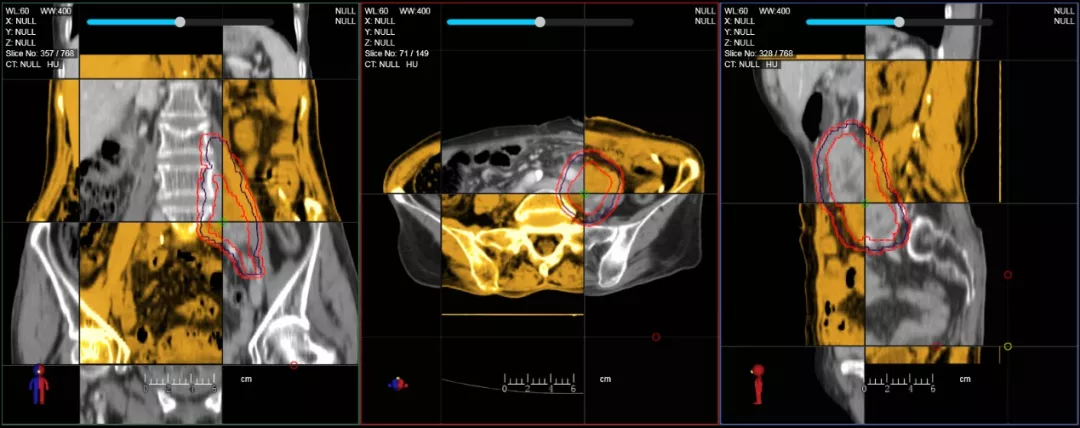

CT-IGRT配準(zhǔn),除骨性標(biāo)記外,還能以器官、軟組織等作為參考,真正找到配準(zhǔn)目標(biāo)

個(gè)體化自適應(yīng)放療

一體化CT-linac讓自適應(yīng)放療ART概念變?yōu)楝F(xiàn)實(shí)。患者全療程狀態(tài)監(jiān)控,適時(shí)在線調(diào)整治療計(jì)劃,精準(zhǔn)控制治療劑量,為患者動態(tài)定制個(gè)體化治療方案。uAI賦能智能勾畫和自動計(jì)劃,秒級勾勒靶區(qū)和危及器官,大幅縮短自適應(yīng)放療時(shí)間。

在線自適應(yīng)放療流程示意圖